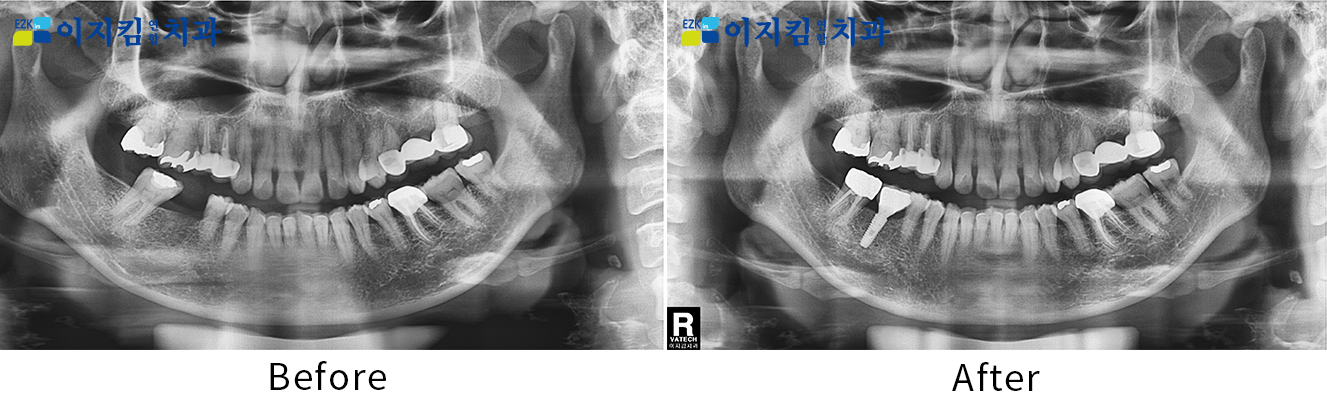

ÀÓÇöõÆ® Àü ¡¤ ÈÄ »çÁø

[

Á¶È¸¼ö : 3163

]